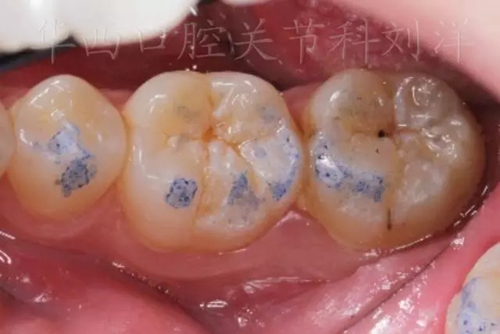

② 然后換用40微米紅色咬合紙,牙尖交錯(cuò)位咬合

▲圖8:40µm 正中咬合